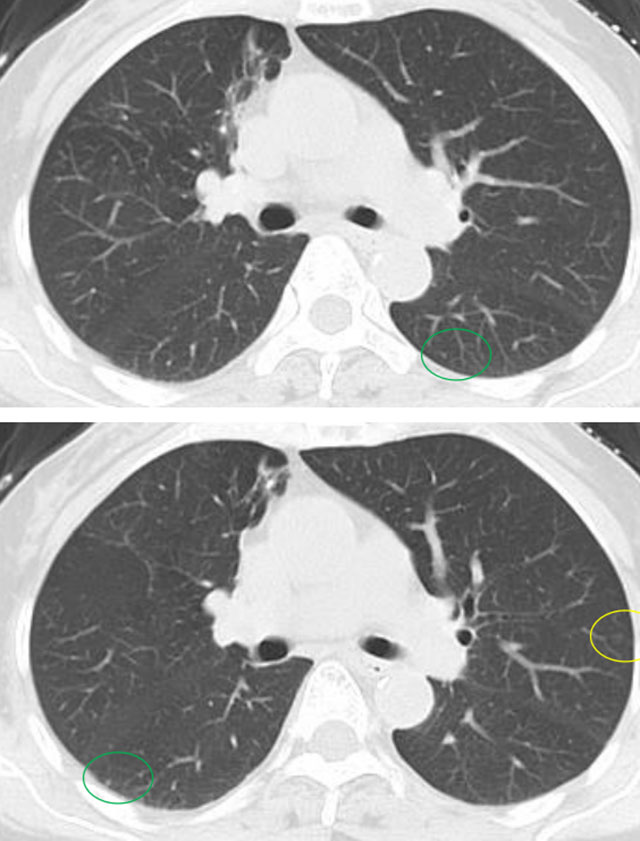

近期,阿姨复查影像展示与分析,1mm层薄层。

与术前及每年复查片对比,阿姨双肺多发磨玻璃结节,均未见显著改变,左肺上叶前段主病灶亦如此,密度很纯,未见增大及实性成分出现,术后5年虽可见血管弯曲,进展极慢,风险还是相对较低,且右肺上叶已经全切除。双肺多发相对较小磨玻璃密度结节,并且进展极慢、仍纯磨密度。该病灶目前没有必须到手术干预程度,只需6-12月复查随访,若有进展并要有风险增加时再考虑干预处理。